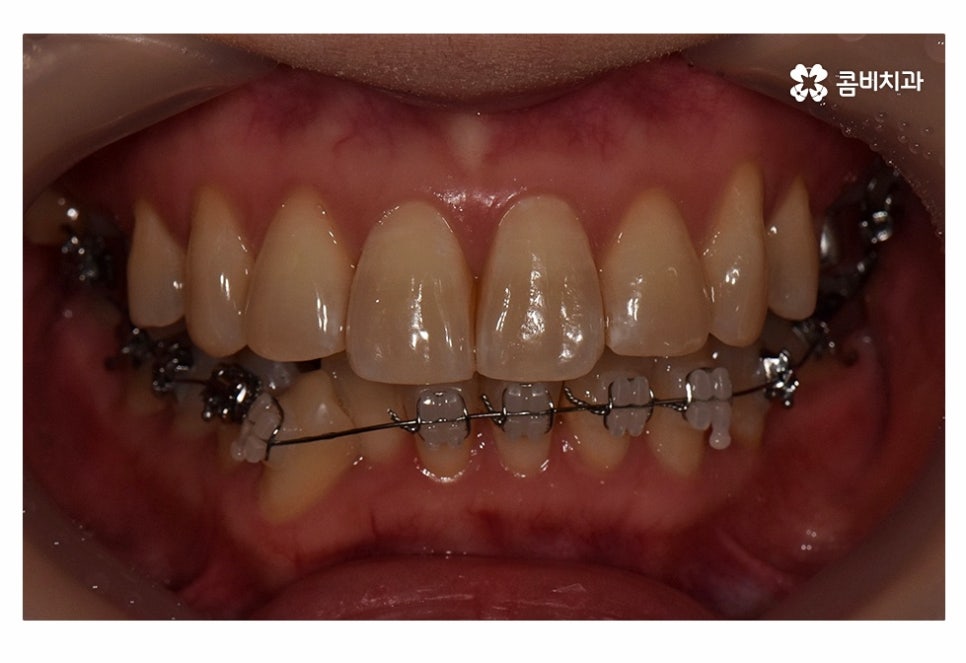

오늘 보실 교정 사례 역시도 윗니는 치아 설측교정으로

진행이 되고 아랫니는 일반적인 순측교정으로 진행되었으며

이러한 치아교정 방법을 콤비교정이라고 부르고 있어요.

사진으로 보시는 환자분의 경우 윗니에 비해

아랫니가 좀 더 불규칙하다는 것을 알 수 있는데요.

위 사진에서 보시는 것과 같이 윗니의 경우 치아설측교정으로

진행이 되고 있기 때문에 교정 장치가 눈에 띄지 않고 있어요.